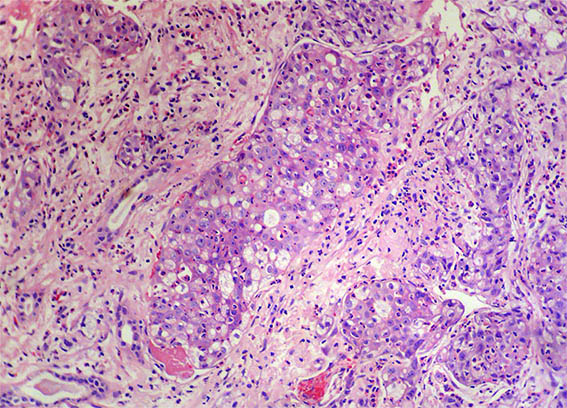

Figura 1. H&E, X100.